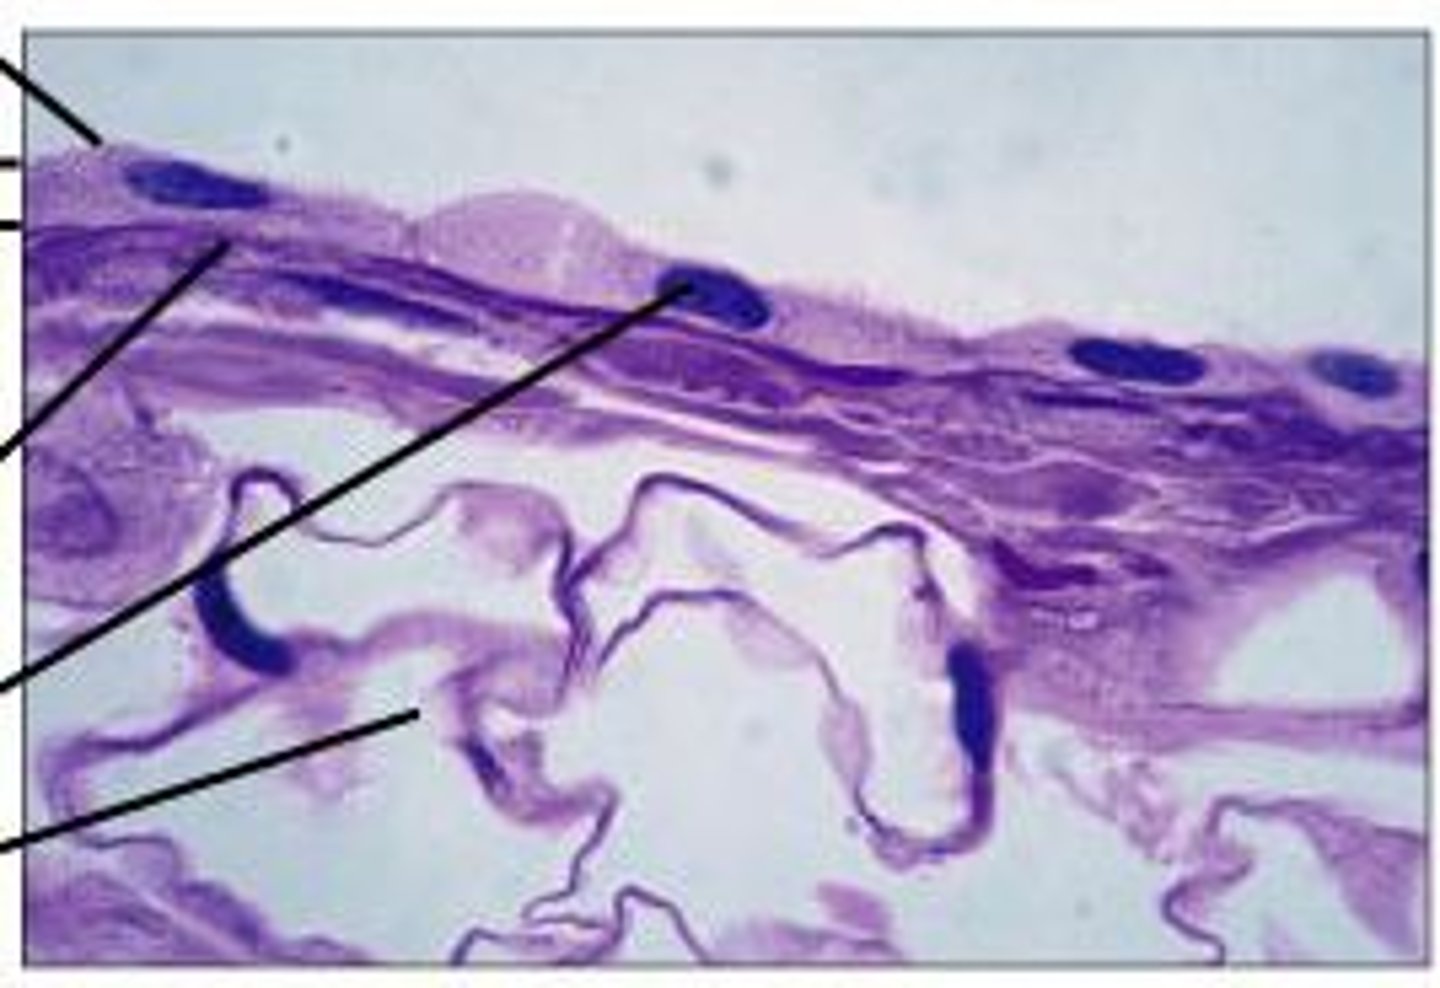

Epithial Tissue

Sheets of tightly packed cells that line organs and body cavities

Cartalige

A usually translucent somewhat elastic tissue that composes most of the skeleton of vertebrate embryos and except for a small number of structures (as some joints, respiratory passages, and the external ear) is replaced by bone during ossification in the higher vertebrates.